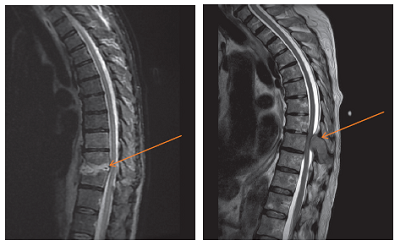

Figure 3 Spine infection (Left); Figure 4 Tumour in the spine (Right)